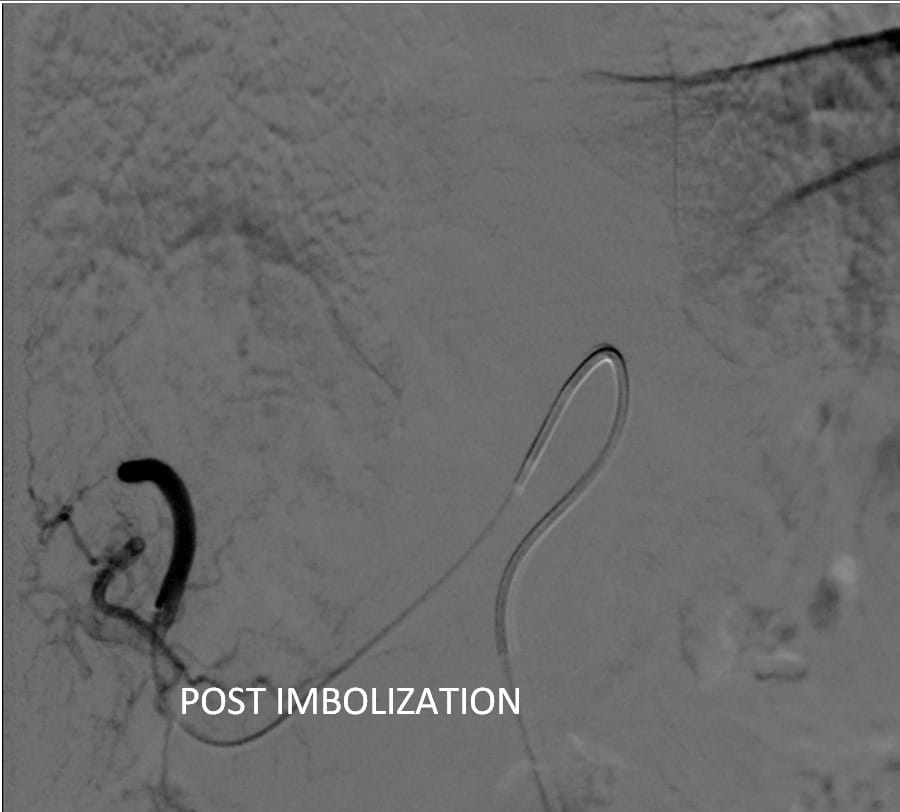

حيث تعد هذه العملية الاولى من نوعها التى يتم عملها من خلال جهاز الأشعة المقطعية ١٢٨ متعدد المقاطع حيث تم علاج الورم من خلال قسطرة بالشريان الكبدي للفص الأيسر من الكبد ونجاح عملية الحقن التي تظهر اختفاء الاوعيه الدمويه المغذيه للورم.